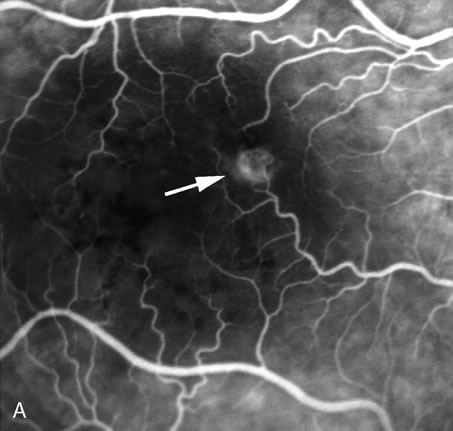

FA is also useful in characterizing two other subgroups of CNV: retinal angiomatous proliferation (RAP)8–16 and polypoidal choroidal vasculopathy (PCV).17–50 RAP begins in the deep retinal complex, forming intraretinal neovascularization (IRN), which may subsequently progress to extend beneath the neurosensory retina, forming subretinal neovascularization (SRN), and a vascularized PED.8 In the later phases of the process there may be a retinal-choroidal anastomosis (RCA). Clinical features of RAP include intraretinal hemorrhages, cystoid macular edema, and associated vascularized PED. FA is useful in revealing the presence of the angiomatous intraretinal vascular complex and the extension of the associated PED (Figs. 12 and 13). However, other diagnostic techniques such as indocyanine green (ICG) angiography, and optical coherence tomography (OCT) may be able to better demonstrate the presence of the RAP lesion.